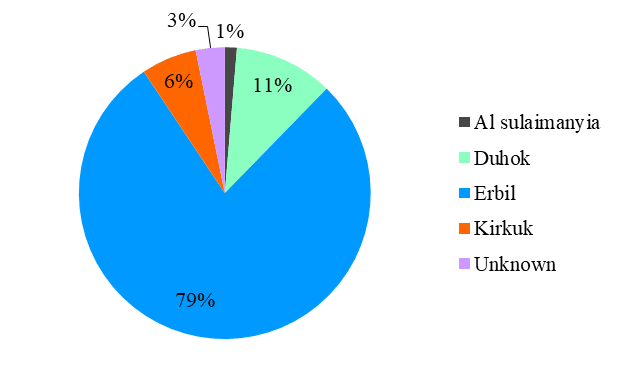

An Insight into the Most Common Cancers in Children Under the Age of 10 Years in Kurdistan, Iraq: A Cross-Sectional Descriptive Study

Childhood cancers are a leading cause of death by disease beyond infancy. In developed countries, leukemia is the most common,...Read More